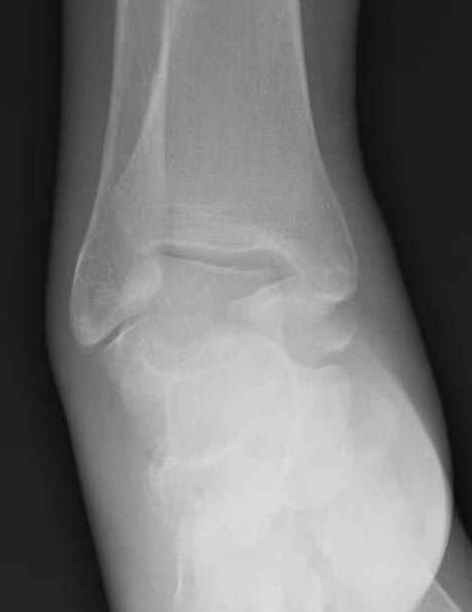

Уважаемые участники русского Ортофорума, поздравляю всех со всеми прошедшими праздниками: Новым годом, Рождеством, Hanukkah, Kwanzaa, желаю участникам всего наилучшего и здоровья.Повреждение таранной кости.Больной 81г автоавария, повреждение таранной кости, здесь снимки. Какие рекомендации?Djoldas Kuldjanov, MDDepartment of Orthopedic SurgerySt. Louis University Medical Center

Вдогонку по поводу перелома таранной кости, больная 81, не страдает диабетом, перелом закрытый, в первый же день поступления ограничились временным наружным фиксатором (как на снимке).

Из-за отека на стопе тактика лечения у всех была

одинаковая: временная наружная фиксация до спадения отека, при изолированных переломах они выписывались домой и через дней 7 госпитализировались на оперативное лечение.

Примеры на снимке...